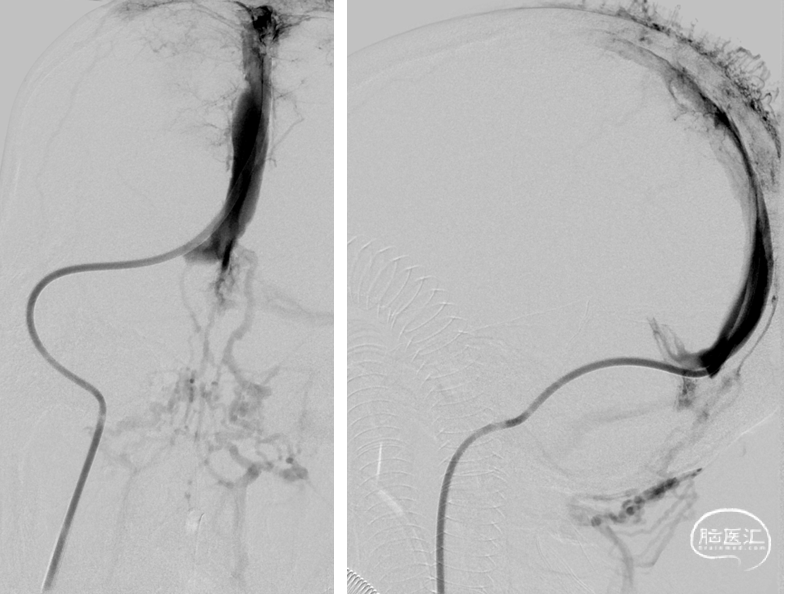

复查造影:上矢状窦显影明显改善,右侧横窦及乙状窦显影良好,静脉回流良好

颅内正侧位造影:上矢状窦显影明显改善,右侧横窦及乙状窦显影良好,静脉回流良好